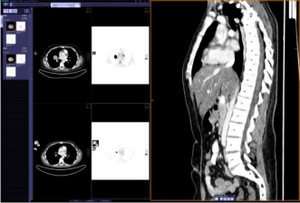

・フィルムレス画像診断を実現する画像作成・表示機能を搭載

1台のシステムで2D-3Dでの操作が可能であり、基本的なMPR*3/MIP*4画像、読影に不要な骨やテーブルを抜いた状態でのVRT*5画像の作成や画像の重ね合わせ(フュージョン)を行うことができる。さらにボリューム体積の計測や肋骨・椎体の位置ラベルのワンボタンでの自動表示など、フィルムレス診断に必要な画像表示機能を装備している。これらの機能により、3Dワークステーション端末を使用することなく日常の読影が可能となり、読影効率の向上とスタッフの業務負担の軽減が実現されるという。

*3 MPR(Multi Planar Reconstruction:任意多断面再構成)。ボリュームデータをある平面で切出して再構成した画像

*4 MIP (Maximam Intensity Projection:最大値投影法)。ある投影部分のCTの最大値表示する方法

*5 VRT (Volume Rendering)。領域抽出を必要とせず、3次元データから直接立体画像を作成する方法